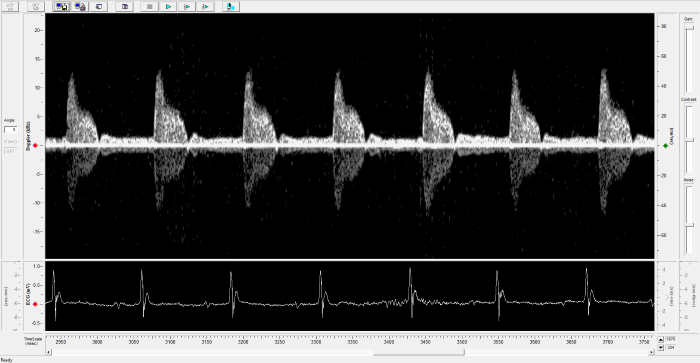

Imaging gallery - Doppler Flow Velocity System

Carotid Image. Image Credit: Scintica Instrumentation Inc.

Mouse - TAC Procedure Imaging. Image Credit: Scintica Instrumentation Inc.

Mouse - Coronary Flow Reserve Imaging. Image Credit: Scintica Instrumentation Inc.

Rat - Left Carotid. Image Credit: Scintica Instrumentation Inc.

Rat - Transverse Aorta. Image Credit: Scintica Instrumentation Inc.

Rat - Right Carotid. Image Credit: Scintica Instrumentation Inc.

Rat - Abdominal Aorta. Image Credit: Scintica Instrumentation Inc.

Mouse - Left Anterior Descending Coronary Artery. Image Credit: Scintica Instrumentation Inc.

Mouse - Left Carotid. Image Credit: Scintica Instrumentation Inc.

Mouse - Mitral Inflow. Image Credit: Scintica Instrumentation Inc.

Mouse - Ascending Aorta. Image Credit: Scintica Instrumentation Inc.